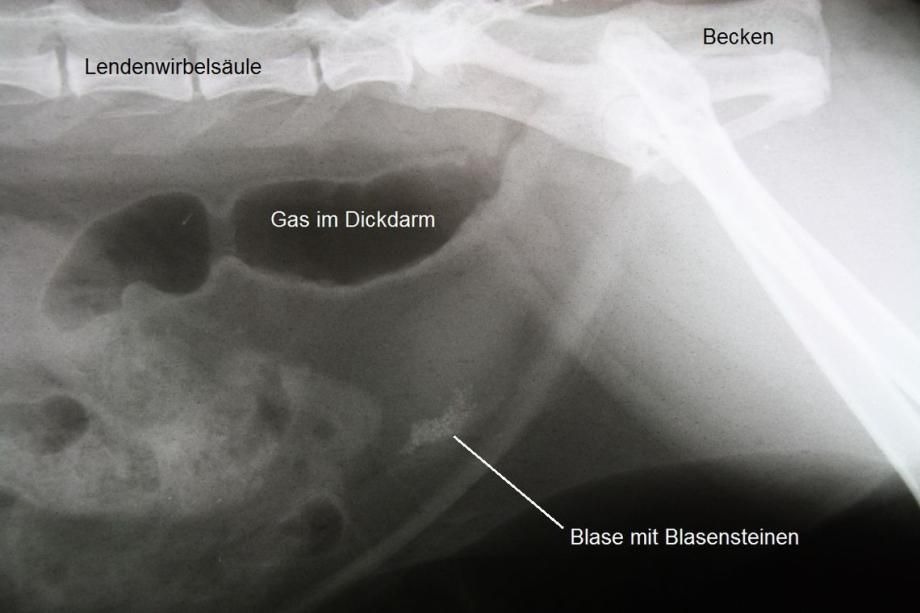

Unter Ultraschallkontrolle wird steriler Urin direkt aus der Blase entnommen und in einem externen Labor bakteriologisch untersucht - es werden aber keine Erreger festgestellt. Hingegen zeigt sich im Ultraschall, dass die Blase Fremdkörper enthält, welche einen Schallschatten werfen. Im Röntgen bestätigt sich die Vermutung, dass die Blase der Katze eine grosse Zahl sehr kleiner Steine enthält, welche röntgendicht ("weiss") erscheinen.

Da Ronja ein weibliches Tier ist, kommt hier eine elegante Methode zur Blasensteinentfernung zur Anwendung: Die Urohydro-Propulsion. Hierbei wird die Blase der Katze unter Narkose mit einem feinen Katheter mit Kochsalzlösung gefüllt. Das Tier wird anschliessend von einer Hilfsperson unter den Vorderbeinen so angehoben, dass die Katze aufrecht in der Luft hängt. Dadurch sammeln sich die Blasensteine im tiefstliegenden Punkt der Blase (dem Blasenhals) und können durch manuelles Auspressen der Blase mitsamt der Kochsalzlösung in die Harnröhre und damit ans Tageslicht befördert werden. Dieser Vorgang wird einige Male wiederholt, bis keine Blasensteine mehr ausgespült werden können. Ein abschliessendes Röntgen bestätigt die komplette Entfernung der mehreren Dutzend Blasensteine.

Blasensteine sind bei älteren Katzen recht häufig zu finden. Je nach Zusammensetzung können die Steine röntgendicht (d.h. "weiss") oder röntgendurchlässig (d.h. "dunkel" und damit im Röntgen nicht erkennbar) sein. Je nach Zusammensetzung kann versucht werden, die Steine mittels Futterwechsel aufzulösen. Da die Blasensteine bei Ronja stark röntgendicht waren, musste davon ausgegangen werden, dass es sich um Calcium-Oxalat-Steine handelte, welche nur mechanisch entfernt werden können. Diese Annahme wurde durch die Untersuchung der Steine nach Entfernung bestätigt.